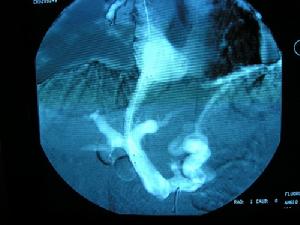

TIPSBalzeretal首次為1例75歲因PHC出血的患者行TIPS治療術前示結腸內見多發的(50個以上)直徑達15mm的血管發育異常病灶術後9d結腸鏡示血管發育異常病灶的數目及大小均明顯減少術後4mo示結腸黏膜規則原病灶完全消失同時胃鏡示原有的胃靜脈曲張及PHG消失;術後隨訪18mo無消化道出血和腦病。